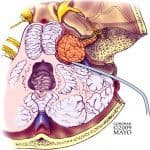

U dây thần kinh VIII – u dây thần kinh ốc tai (vestibular schwannoma / acoustic neuroma / acoustic neurinoma) là u lành tính từ tế bào Schwann, ưu thế ở nhánh tiền đình. Hiếm hơn, u có thể phát triển trực tiếp từ nhánh thính lực. Trong các trường hợp Neurofibromatosis type 2, u phát triển là do mất gene đè nén u trên nhánh dài của NST 22…